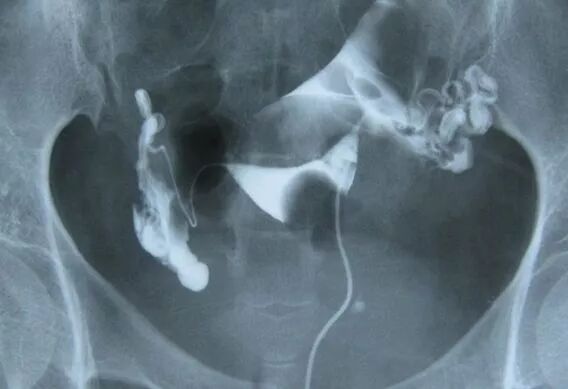

2年以下的不孕症患者,可以先做输卵管通液检查;2年以上的不孕症患者,发生过宫外孕的人,以及做过宫腔镜或腹腔镜手术的不孕症患者,则要进行输卵管造影检查。

做输卵管造影多数人不会感到疼痛

在该做而没做输卵管造影检查的不孕症患者中,有些人因为担心检查痛苦而迟迟不敢做,有些人则认为做完造影检查,要等3个月以后才能考虑要孩子,若检查显示自己的输卵管没问题,岂不是白白浪费了3个月的时间。

其实,做输卵管造影检查,并没有大家想象中那么痛苦。一般不会感觉到疼,和做妇科检查差不多。